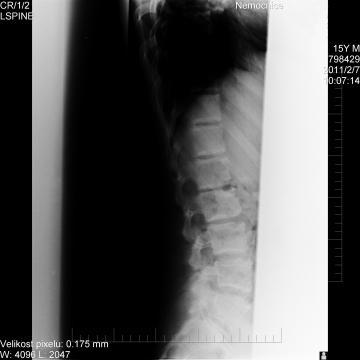

Dobrý den,je mi 16 let a již 3 roky trpím bolestmi zad v oblasti bederní páteře, zvláště při zátěži. Pokud je možné určit diagnozu z přiložené fotografie rentgenu, byl bych vám velmi vděčný. Předem děkuji za odpověď.

Dobrý den,přiložený snímek je pro hodnocení v malém rozlišení. V oblasti berední patéře dle tohoto snímku nevidím žádné abnormality. Příčinou může být tvz. svalová nerovnováha, kdy jsou některé svaly oslabené a jiné jsou zase přetížené) Máte snímek popsaný rentgenologem ? Doporučuji stav konzultovat se svým lékařem, který si RTG snímek L-páteře vyžádal. Blíže se k problému nemohu vyjádřit.